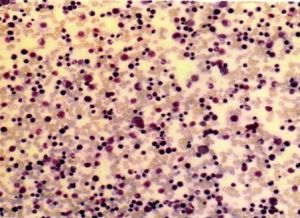

球形紅細胞遺傳性球形紅細胞增多症是一種紅細胞膜先天缺陷的溶血性貧血,其特點為慢性溶血過程常伴有急性發作,循環血液中球形紅細胞增多,紅細胞滲透脆性增高,並有不同程度的脾腫大和黃疸。

外周血塗片球形紅細胞明顯增多